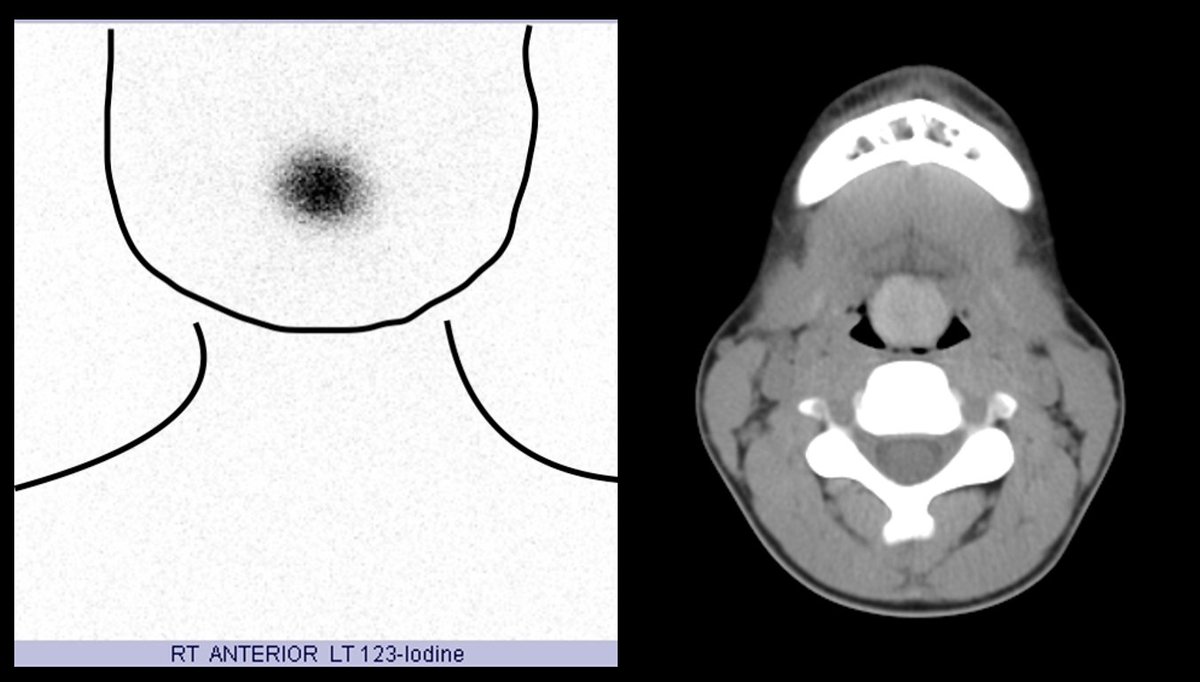

Case Challenge: # 57

Test your skills by providing answers in comments. Come back to check the answer key in 24 -48h.

Get all the cases at: nuclearmd.com/courses